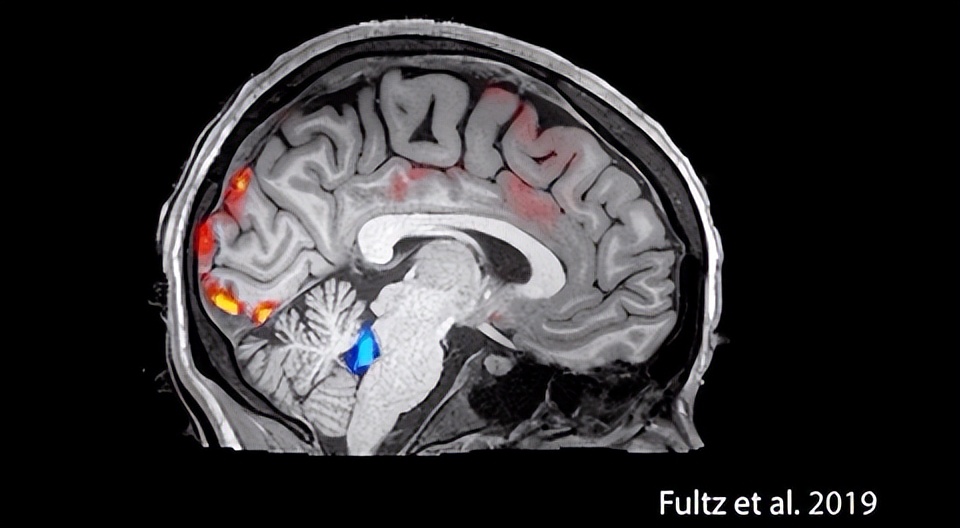

白天工作时大脑中会产生代谢废物,晚上睡眠时脑脊液将开始“清理模式”,给大脑洗澡,洗掉这些有害的物质,从而让大脑恢复活力。2019年波士顿大学的一项研究,清晰地描绘出睡觉时脑脊液清除这些代谢废物的整个过程。

波士顿大学研究发现脑脊液的工作过程(图源:文献《Coupled electrophysiological, hemodynamic, and cerebrospinal fluid oscillations in human sleep》